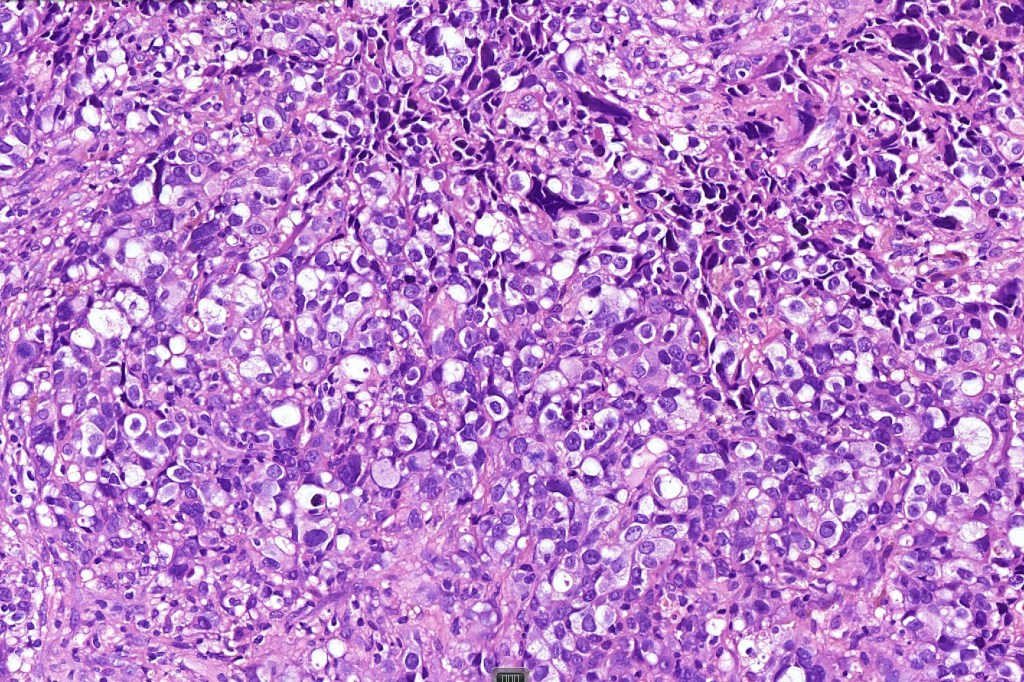

These are very rare variants of amelanotic or virtually amelanotic melanoma where a primary melanoma or a metastasis shows partial (DN) or complete loss (UN) of recognizable histological and immunohistochemical features. The histology may lead the pathologists to consider lymphoma, sarcoma, anaplastic carcinoma or a small cell tumor. Some examples of rhabdoid melanoma & melanoma with heterologous differentiation probably belong in this category. Ultimately, if there is no identifiable/recognizable primary tumor, diagnosis may only be comfortably made with next-generation sequencing. In the cases presented below, immunohistochemistry was of value in determining the melanoctic nature of the tumor (undifferentiated melanoma).